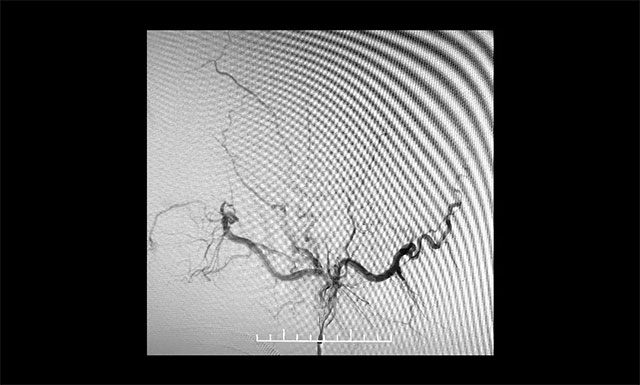

DSA 检查显示,左侧天幕区硬脑膜动静脉瘘,瘘口血流大,供血来源广泛,引流静脉有瘤样扩张。

▲ DSA检查显示,左侧天幕区硬脑膜动静脉瘘